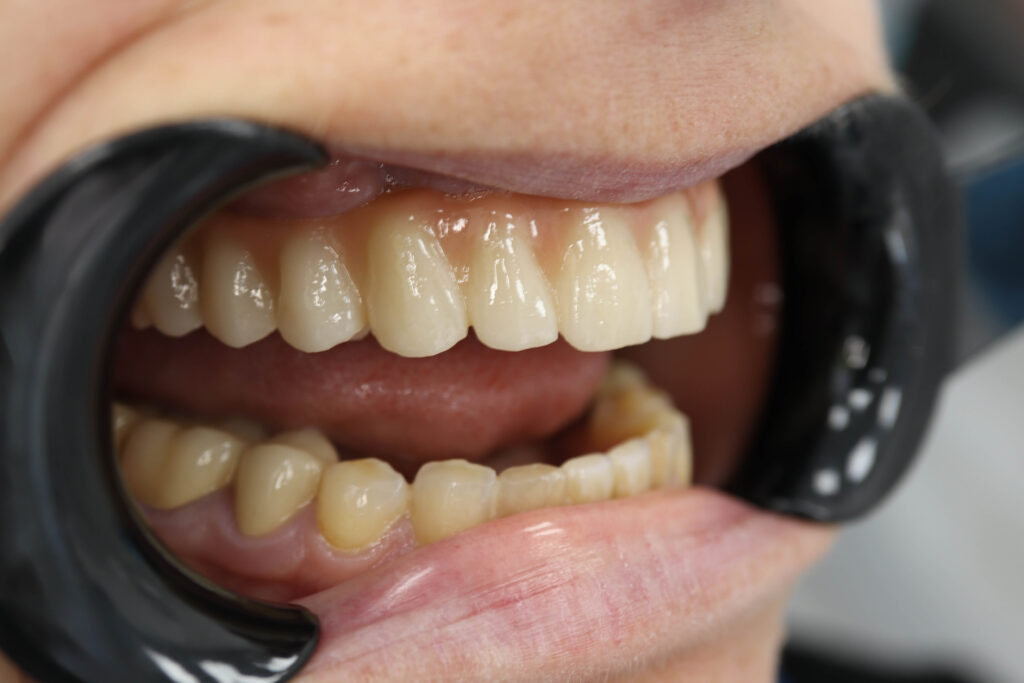

Спустя 25 дней был зафиксирован протез с опопрой на дентальные имплантаты из диоксида циркония.

Результаты

снимок